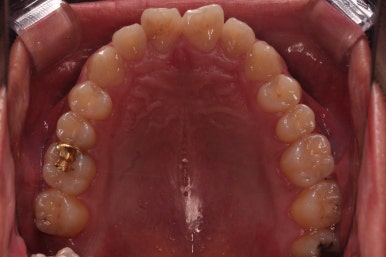

초진 시 입안의 모습입니다.

비교적 고른 편이긴 하나 아랫니가 전반적으로 밀려 나오면서 앞니끼리 부딪혀 있는 양상이고요.

어금니 맞물림도 긴밀하게 톱니바퀴처럼 위아래가 맞물려 있는게 아니라 엉성한 모습이죠.

앵글씨 3급 부정교합이라고 하는데요.